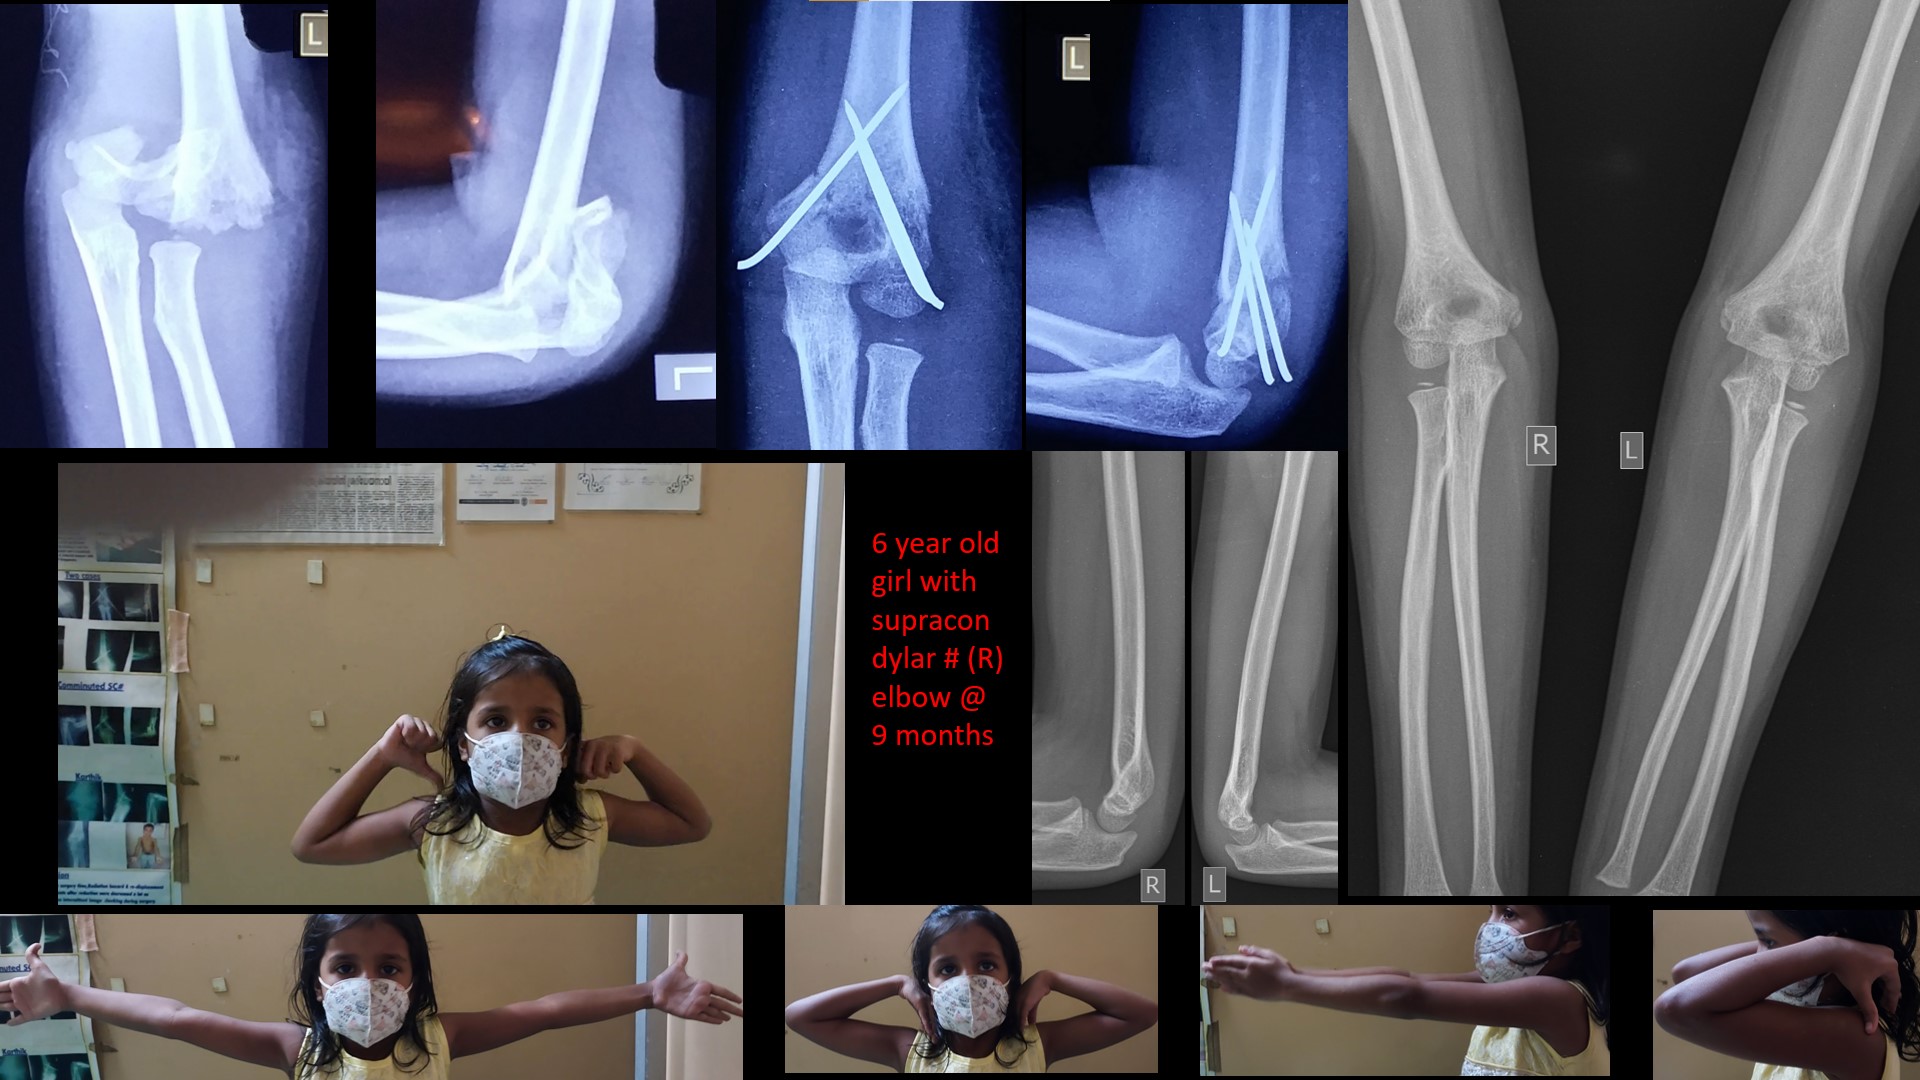

SUPRACONDYLAR #